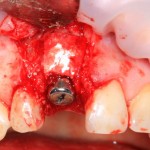

Немедленная имплантация — оптимальное решение в любой клинической ситуации